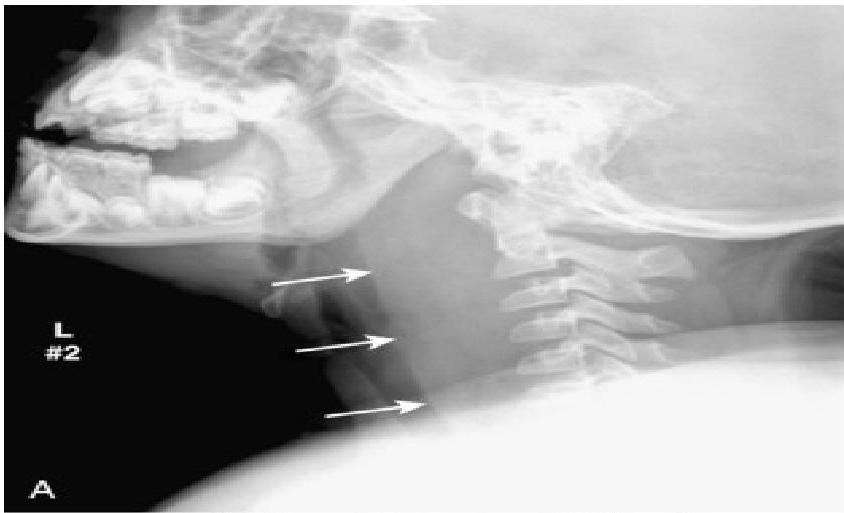

- Soft-tissue Lateral Neck Radiographs:

- Portable if possible.

- Positive in 80% of cases.

- Feature: An enlarged epiglottis protruding from the anterior wall of the hypopharynx (the “thumb sign”).

- Other findings: Thickened aryepiglottic folds, loss of vallecular air space, distended hypopharynx.

- X-ray: Look for the thumbprint sign.